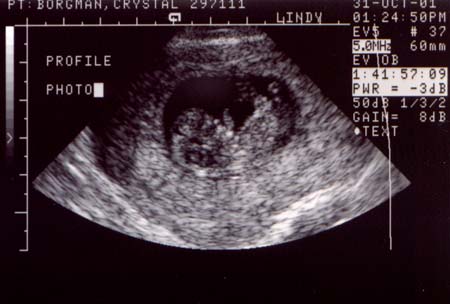

First ultrasound.

The baby looks great! It was moving around and having

a good old time. It measured at 10 weeks and 4 days,

or 37 millimeters (about 1 1/2 inches), which is just

about right. The heart rate was 188 bpm and very strong.

Looks like we've got a keeper.

Ultrasound Pictures:

Photo from top of

head looking down, baby's legs are crossed

Large

- 900x720 pixels / 66.1K

Small

- 450x360 pixels / 28.2K

head looking down, hands are together

- 900x700 pixels / 68K

- 450x350 pixels / 28.8K

Side profile, jaw

bones are prominent (the light areas)

- 900x720 pixels / 71.3K

- 450x360 pixels / 30.3K

Side profile, with

hand by face

- 900x600 pixels / 63.1K

- 450x300 pixels / 26.8K |